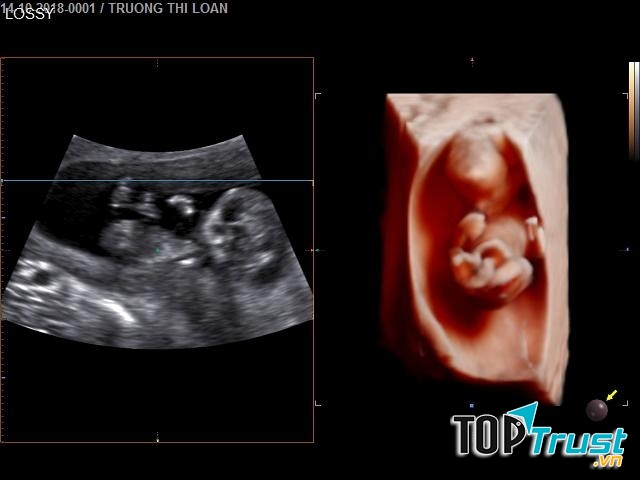

SIÊU ÂM 5D - PGS Nguyễn Phước Bảo Quân

SIÊU ÂM 5D - PGS Nguyễn Phước Bảo Quân là địa chỉ tin cậy nhất để các bạn có thể tin tưởng đến kiểm tra sức khỏe sinh sản của mình, với môi trường chuyên nghiệp và hiện đại, đặc biệt bệnh viên là nơi hội tụ đầy đủ các bác sỹ khoa sản có trình độ học vấn chuyên môn cao cùng với kinh nghiệm dày dặn trong quá trình làm việc của mình, các bác sỹ sẽ chuẩn đoán được cho bệnh nhân những triệu chứng bệnh chính xác nhất từ đó xác định được nguyên nhân gây bệnh và biện pháp điều trị kịp thời.

Lý do để bạn chọn SIÊU ÂM 5D - PGS Nguyễn Phước Bảo Quân:

- Đội ngũ y bác sỹ có trình độ chuyên môn cao và giàu kinh nghiệm, tâm huyết với nghề

- Cơ sở vật chất hiện đại, hệ thống máy móc trang thiết bị mới, được nhập khẩu từ nhiều nước trên thế giới đảm bảo độ chính xác cao